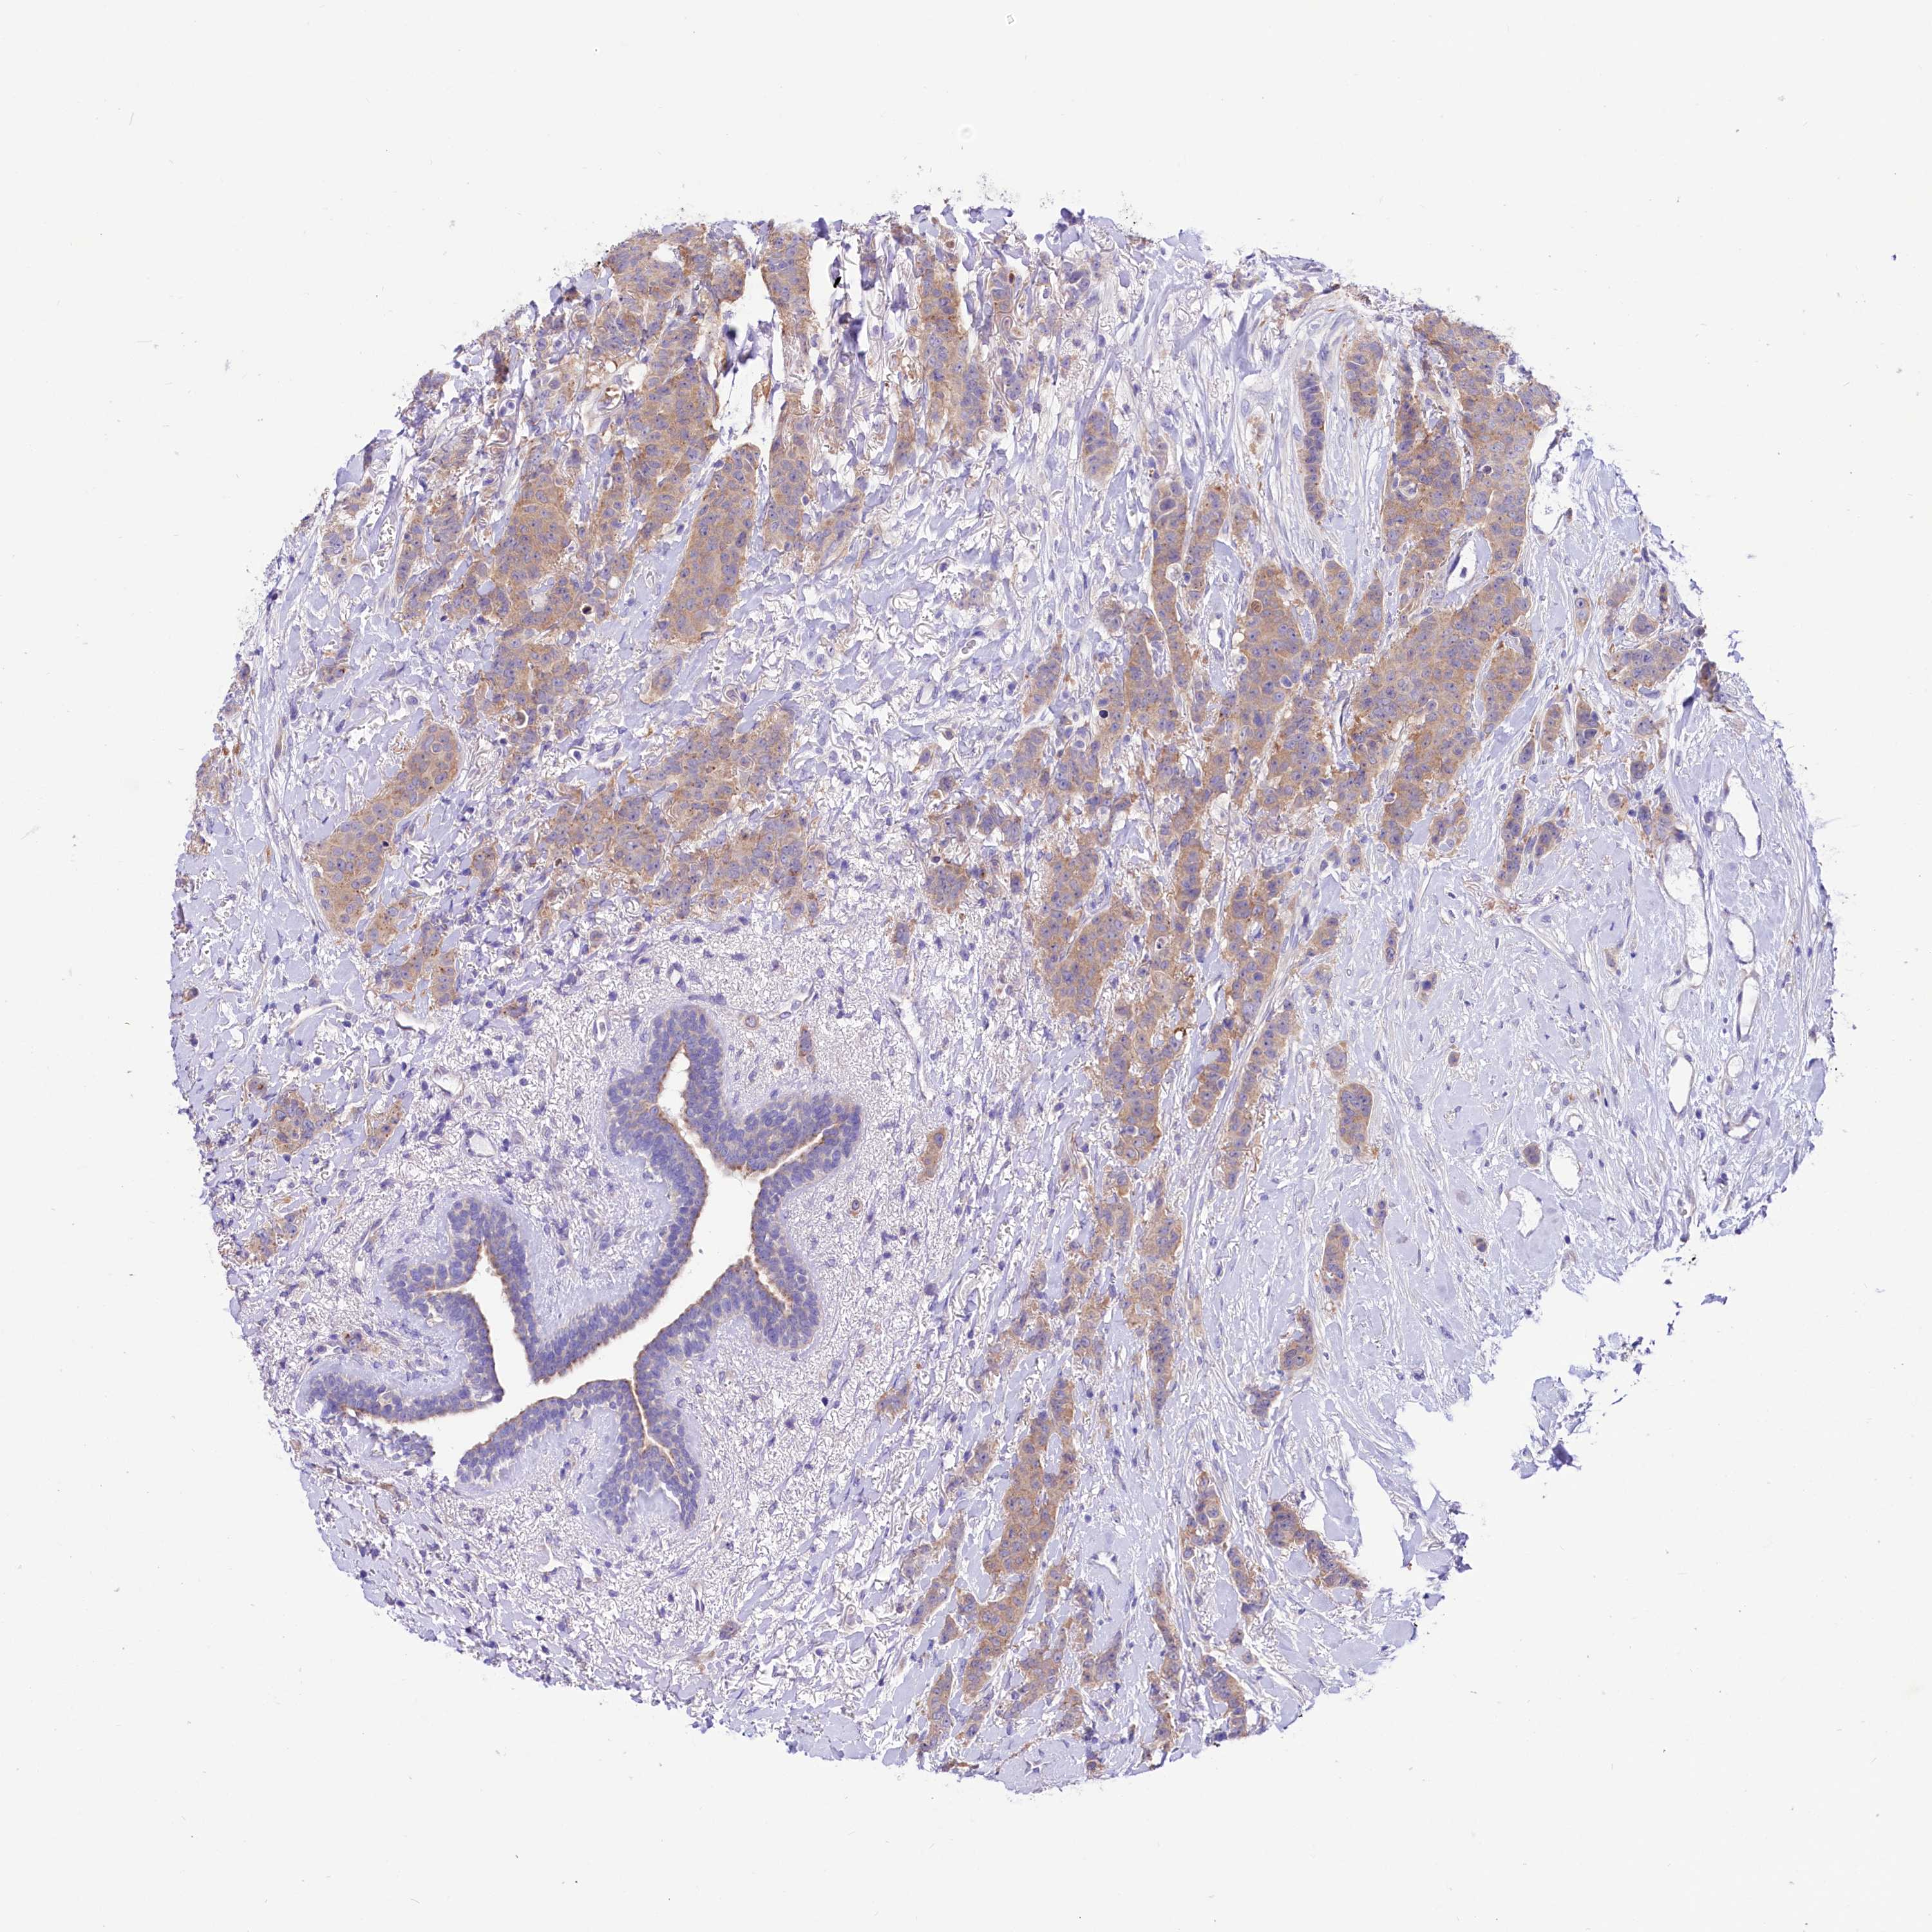

BRCA TCGA BRCA VALIDATION PROTEIN EXPRESSION

Breast cancer

Human cancer